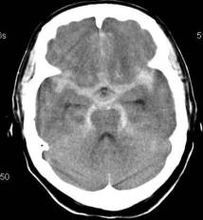

1.CT

CT被認為是蛛網膜下腔出血的首選檢查,且能確定出血範圍、血腫大小、腦梗死等,有助於動脈瘤的定位。CT檢查中密度不同的同心環圖像“靶環征”是巨大動脈瘤的特徵性表現。目前CTA主要用於動脈瘤的診斷和夾閉術後的複查。